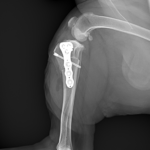

CBLO #248

性の前十字靭帯断裂の中型犬にCBLOで安定化を実施しました。慢性経過のためミディアルバトレスが分厚くなって触知することが可能です。また関節内を探査すると、内側半月板の尾側領域はダブルバケットハンドルという状態で亀裂が2ヶ所確認されました。しばらくは安静が必要です。